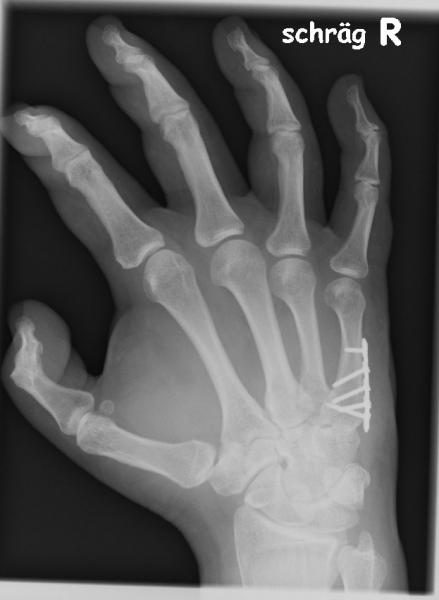

Hand

Bild: Hand

Bildbeschreibung: Metallversorgte Mittelhandfraktur

Chirurgen haben wohl etwas bei "Zimmerern" beim Dachstuhlbau abgeschaut ??